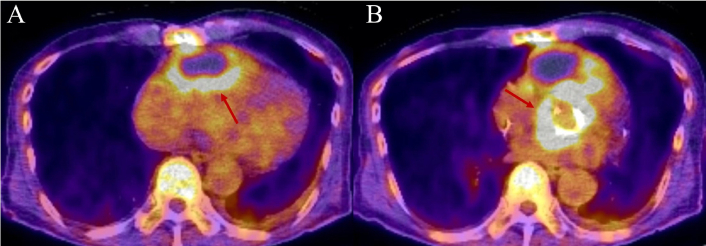

In PVE, 18F-FDG-PET/CT significantly improves sensitivity and specificity, with pooled sensitivities of 85–93% and specificities of 85–95%. It is particularly valuable in reclassifying “possible” cases and is most effective when performed early, prior to significant antibiotic exposure. Representative patient cases are shown in Figure 5 to illustrate their clinical utility. Quantitative metrics such as standardized uptake value (SUV) ratios add to diagnostic precision. WBC-SPECT/CT is also effective in identifying inflammation and perivalvular abscesses, although its sensitivity is generally lower than PET/CT [65, 67]. In TAVR-IE, PET/CT is increasingly utilized to identify prosthetic infections and systemic septic emboli. However, interpretation is challenging early post-implantation due to inflammation-related false positives. Diagnostic accuracy is generally lower than for surgical valves, necessitating careful correlation with clinical and other imaging data [61, 68].

PET/CT imaging of prosthetic aortic valve endocarditis. This is the case of a 70-year-old male patient with a complex cardiac surgical history, initially undergoing aortic valve replacement with a #25 Inspiris valve, along with ascending aorta and hemiarch replacement, and saphenous vein graft (SVG) bypass of the ramus coronary artery due to aortic intramural hematoma. A few years after the initial surgery, the patient developed prosthetic aortic valve endocarditis with an aortic root and right ventricular free wall abscess. Panel A: PET/CT axial view highlighting a large cystic mass located in the anterior pericardial region. The mass exhibits increased peripheral 18F-FDG uptake with a maximum standardized uptake value (SUV) of 5.6 and central photopenia, which is suggestive of an abscess. Red arrow is pointing to the area of increased uptake. Panel B: PET/CT axial view at the level of the aortic valve demonstrating heterogeneous increased 18F-FDG uptake with a maximum SUV of 12.4. The uptake corresponds to soft tissue density surrounding the prosthetic valve, raising suspicion for active infection. Red arrow is pointing to the area of increased uptake. PET: positron emission tomography; CT: computed tomography; FDG: fluorodeoxyglucose.